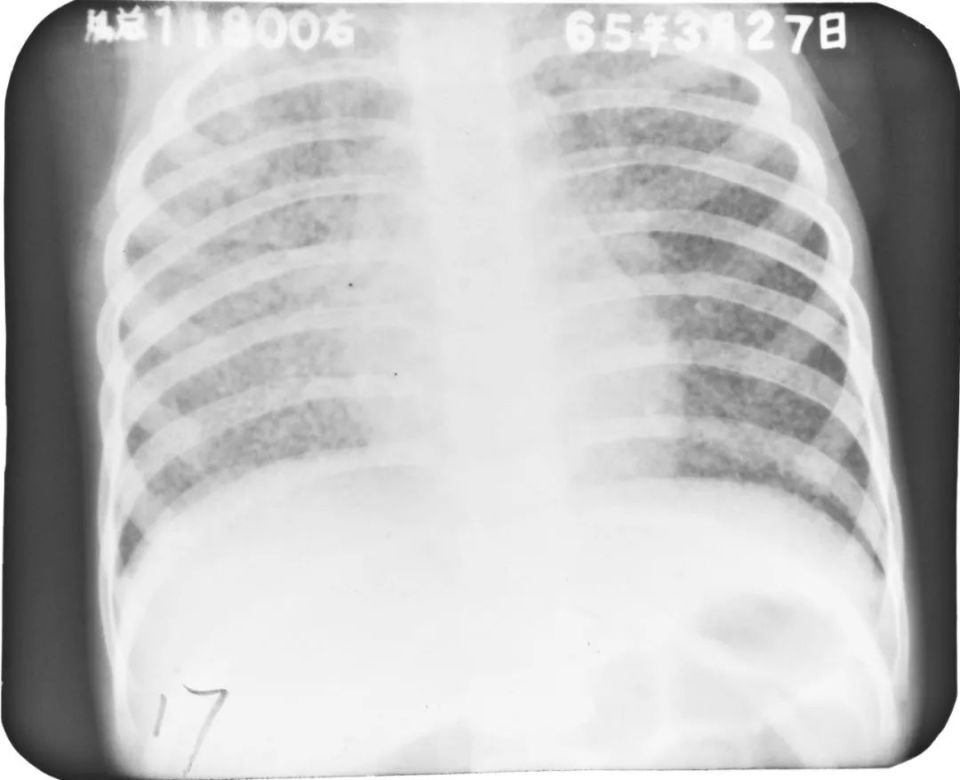

急性粟粒型肺结核(三均匀)

图片

胸部正位片:两肺弥漫性分布大小不等的、分布均匀的粟粒状密度增高影,边缘模糊